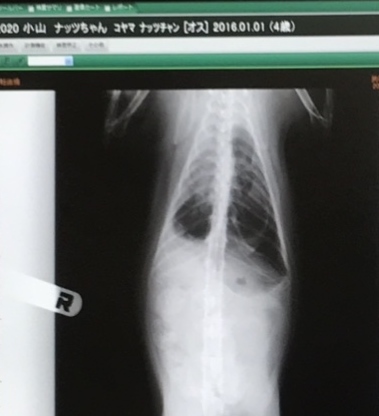

胸のあたり白くくもっているところがお水がたまっている箇所です。

健康な猫ちゃんは黒く空洞がしっかり映ります。

空洞ももっと範囲が広いです…

お水を抜いて3日後にレントゲン検査してもらいました!!

最初の画像より少し胸が綺麗になっていて投薬が効いている感じです!

ただ左側がまだ白くくもっています。